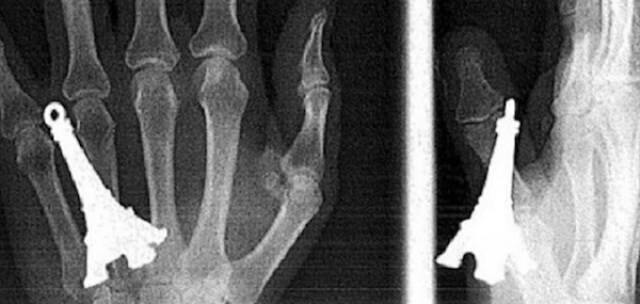

15. Модель Ейфелевої вежі у руці